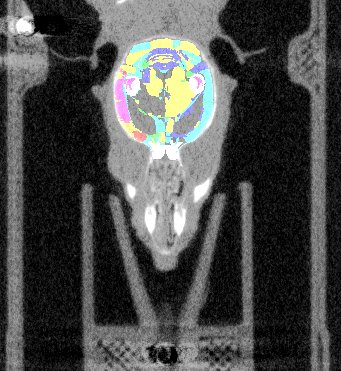

| Overlay of co-aligned CT scan and brain atlas-staining | Overlay of co-aligned CT scan and DAPI-staining | Overlay of co-aligned brain Atlas and DAPI-staining |